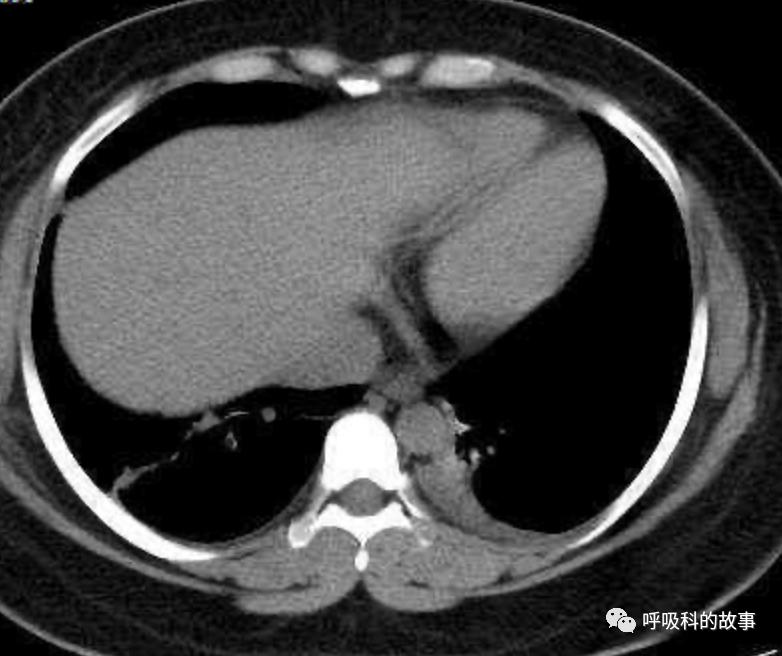

可是在6月26日(往院第18天)仍持续发热的情况下复查肺部CT,肺部病灶已明显吸收了。那么患者发热的原因到底是什么呢?为什么患者高热的情况下血白细胞不升反降,C反应蛋白也没有明显增高?这个时候消化科医生也迷茫了,这可怎么办?于是请感染科和呼吸科医生一起会诊,共商计策。